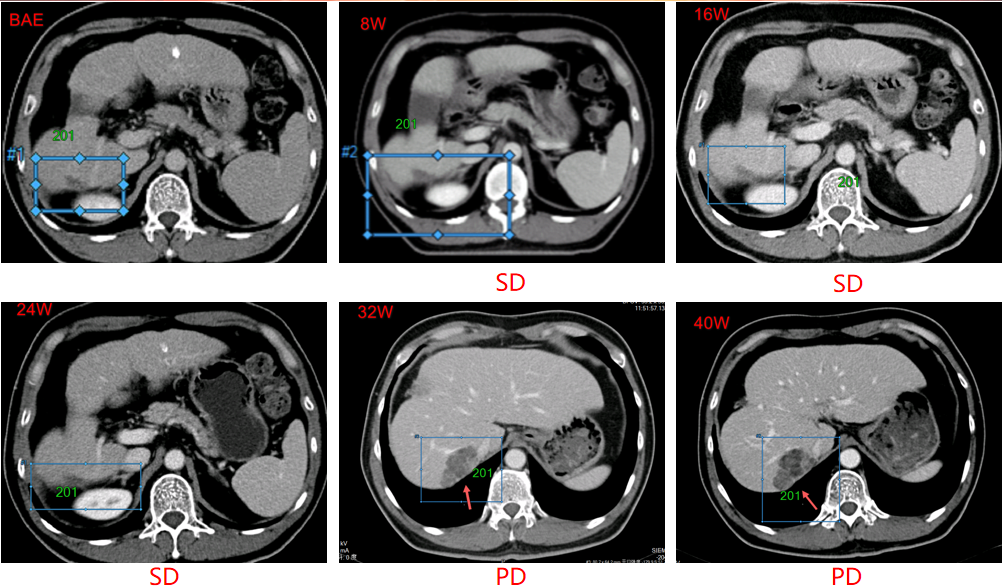

靶病灶影像学改变

2016-11-15,首次口服多纳非尼治疗(0.2g,每日两次口服),肿瘤些许增大,疗效评估为疾病稳定(SD),继续接受多纳非尼治疗,肿瘤持续稳定。经独立审查委员会(IRC)评估的无进展生存期(PFS)为7.5个月,经研究者评估的PFS为9.3个月。